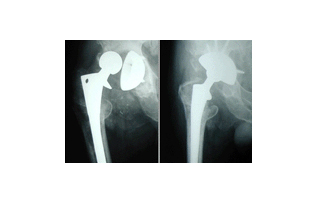

- 인공관절 치환술: 가장 일반적인 고관절 수술입니다. 퇴행성 관절염이나 심한 외상으로 인해 고관절이 손상된 경우, 인공 관절로 대체합니다. 이 수술은 대개 1-2시간 가량 소요되며, 회복이 길어질 수 있습니다.

각 수술 방식에 따라 환자의 상태를 고려한 특화된 치료 계획이 필요합니다. 예를 들어, 인공관절 치환술을 받을 경우에는 십여 주의 회복 기간 동안 물리 치료와 약물 치료가 반드시 포함되어야 합니다. 반면 관절경 수술의 경우에는 초기 회복 단계에서의 가벼운 운동과 체중 부하가 더 강조될 수 있습니다.